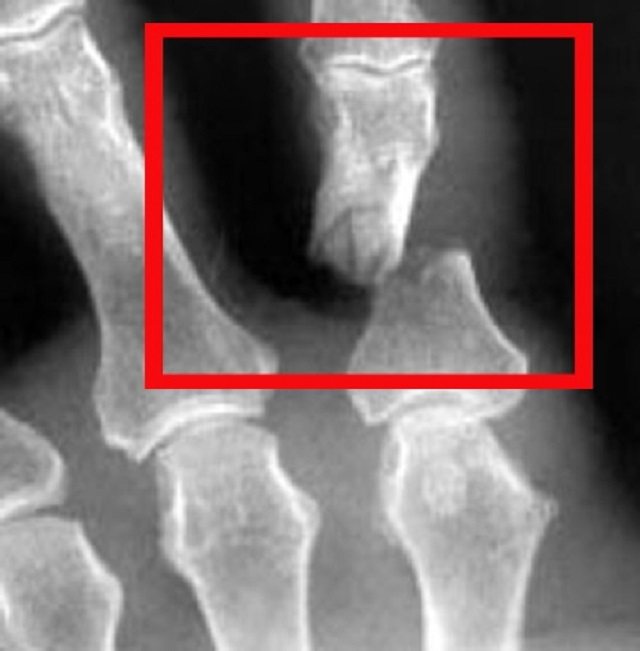

Рентген имеет большое значение в постановке правильного диагноза

- От удара ломается фаланга пальца. Переломы мизинцев часто схожи на ушибы, особенно если они происходят без смещения. Но при переломе мизинца попытка согнуть палец приносит сильные болевые ощущения. Лучше всего определить перелом пальца поможет рентген.

Для окончательного исключения перелома пациента направляют на рентгенологический снимок пальца, в сложных случаях могут провести компьютерную томографию кости.

Диагноз «разрыв сухожилия» может быть после проведения осмотра пациента и после того, как снимут рентген.